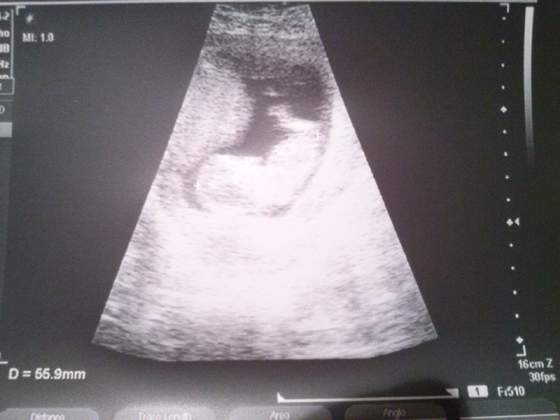

Wczoraj wyszłam z koleżanką na kawę, później przyszłyśmy do mnie bo mąż chciał pobiegać, a jak Nela spać poszła to oczywiście kłótnia... Dziś po jego pracy to samo. Kurcze mam już dość. W dodatku powiedziałam mu w końcu, co czuję odnośnie posiadania syna... To kazał mi do psychologa iść, wkurzył się potwornie. Dziś mamy niby jeszcze rozmawiać na ten temat, ale co ja poradzę że nie potrafię się cieszyć, że będziemy mieli syna? Nie miałam pojęcia, że moja niechęć do chłopców aż tak na mnie wpłynie... Wydaje mi się, że ja nigdy nie chciałam mieć syna ze względu na mojego ojca- zawsze widziałam w nim ucieleśnienie najgorszego wychowania, wiedziałam że dziadkowie zrobili z niego takiego człowieka, przez co ja od zawsze mam w głowie, że synowie są tacy do niczego...